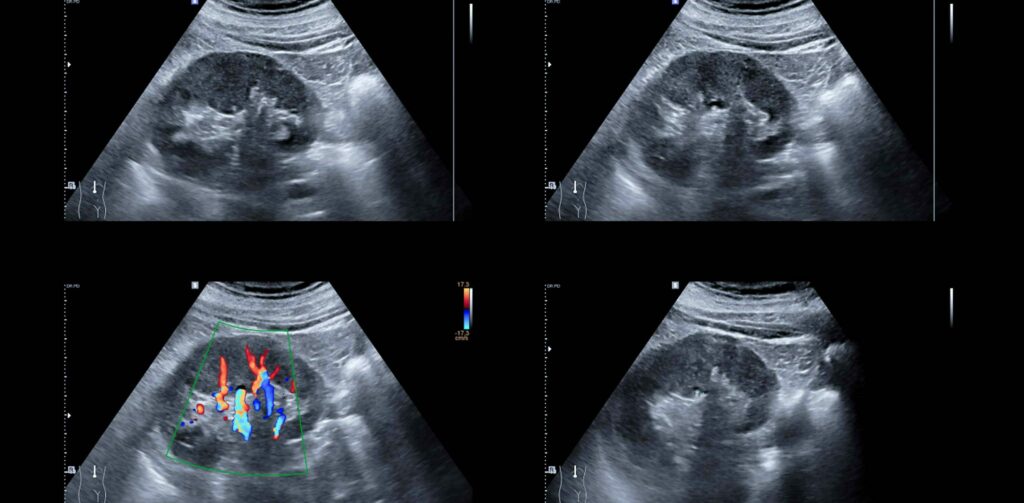

A portable AI-enabled ultrasound system is being developed to help health workers monitor and identify high-risk pregnancies in low-resource settings by using an AI engine in combination with advanced image processing. Our client is developing a market-ready Software as a Medical Device (SaMD) product, using an off-the-shelf ultrasound probe connected to a user-supplied tablet.